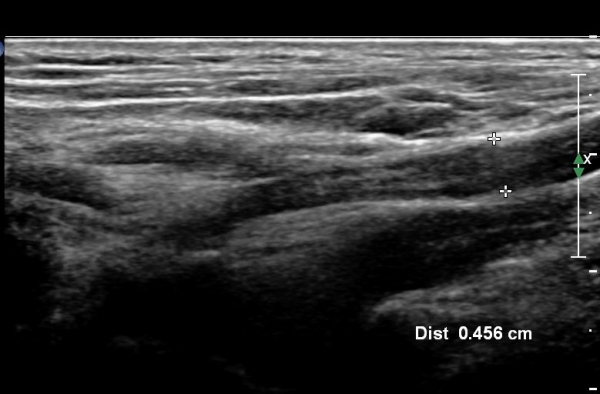

ŽÃËÀÚ¸¦ Á¶±Ý ¸»´ÜÀ¸·Î À̵¿ÇÏ¿© Àü»ç°¢±Ù°ú Á߻簢±Ù »çÀÌ¿¡¼­ »ó¿Ï½Å°æÃÑÀÇ Àú¿¡ÄÚ ºÎÁ¾ÀÌ °üÂûµÊ                  (»çÁø 2, 3).

¸ñ ¾Õ ¿ÜÃø¿¡¼­ Á¦5, 6 ½Å°æ±Ù Á¾´Ü¸é°Ë»ç¿¡¼­ Á¦5, 6 ½Å°æ±ÙÀÇ Àú¿¡ÄÚ ºÎÁ¾(4,5mm, 6.5 mm)ÀÌ

°üÂûµÇ°í »çÁø 4,5 ) °ÇÃø(»çÁø 6, 7)(2.4mm, 3.1mm)°ú ºñ±³ÇÏ¸é ¾à 2¹èÀÌ»ó ºÎÁ¾ÀÌ ¶Ñ·ÇÇÔ.